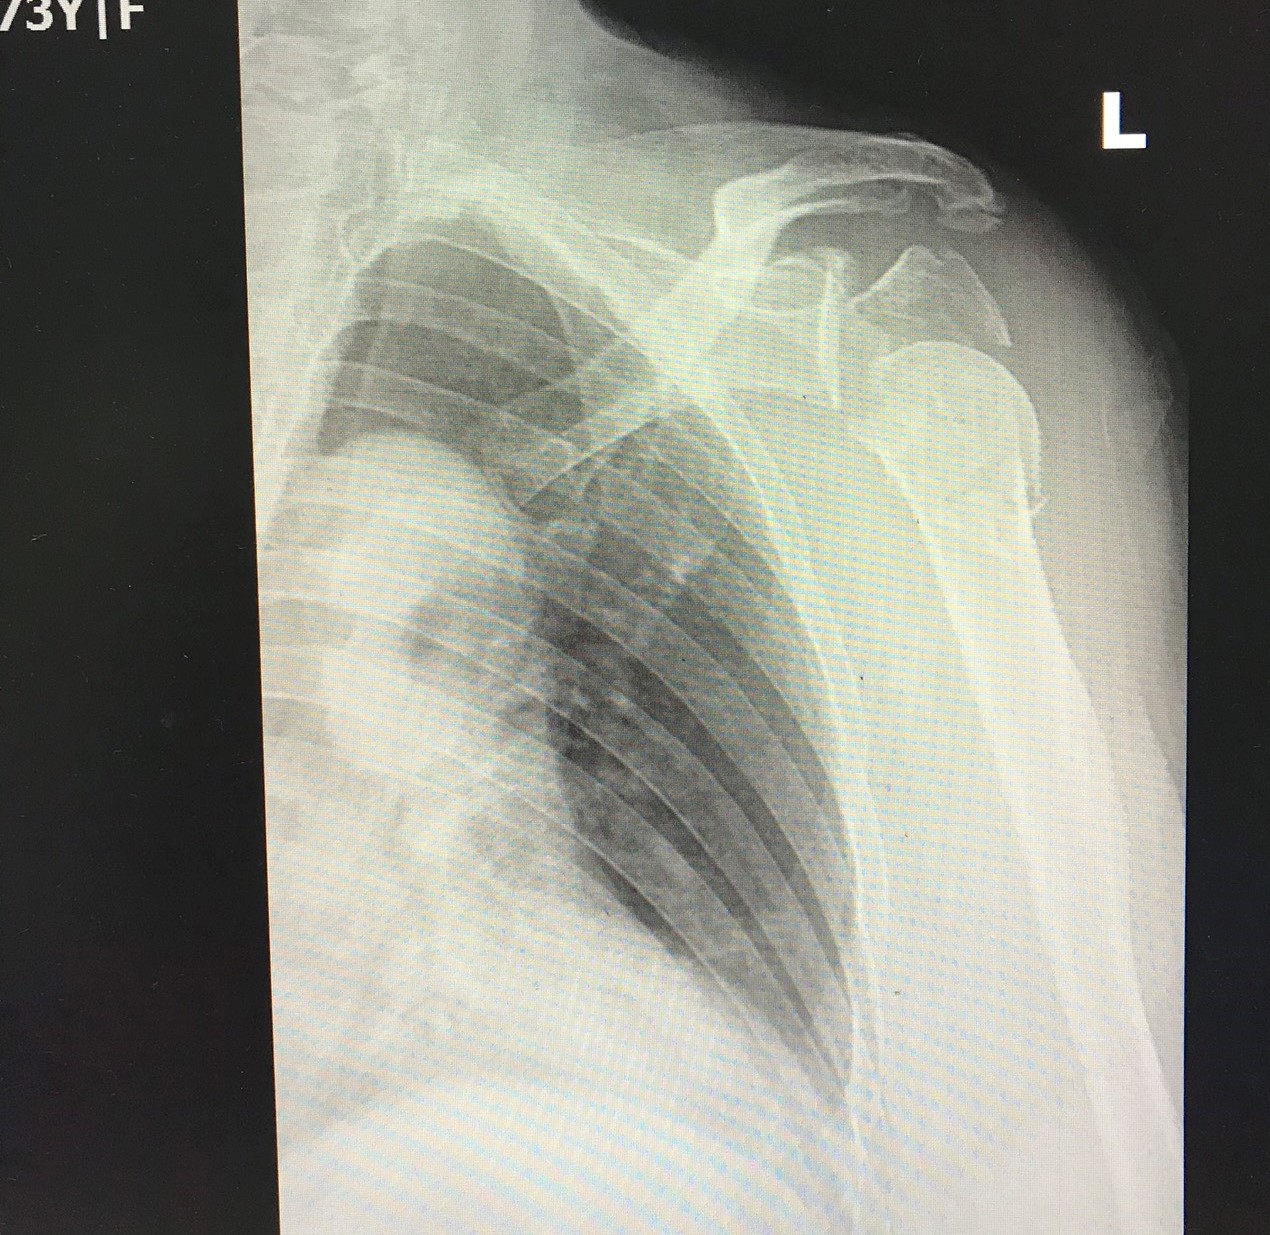

Bệnh nhân Trần Thị C, 73 tuổi, ở Vạn Mỹ, Ngô Quyền, Hải Phòng bị tai nạn giao thông ngã đập mạnh vai trái xuống đường. Sau tai nạn bệnh nhân đau và không thể cử động khớp vai bên trái. Vào cấp cứu tại Bệnh viện đa khoa Quốc tế Hải Phòng, qua thăm khám và chụp phim X-quang, các bác sĩ kết luận bệnh nhân bị gãy phức tạp đầu trên xương cánh tay kèm trật khớp vai trái. Trên nền thể trạng bệnh nhân già yếu, kèm theo các bệnh lý nền: tăng huyết áp, đái tháo đường type 2, hội chẩn liên chuyên khoa Ngoại – Nội tiết – Tim Mạch – Gây mê hồi sức nhanh chóng được diễn ra nhằm đưa ra hướng điều trị tốt nhất cho bệnh nhân. Sau hội chẩn, các bác sĩ đã quyết định chọn phương pháp phẫu thuật thay khớp vai trái bán phần cho bệnh nhân.

- Hình ảnh gãy phức tạp đầu trên xương cánh tay kèm trật khớp vai trái trước mổ của bệnh nhân